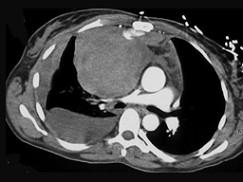

男,33岁,右胸部外伤,胸闷、气短,结合CT图像,最可能的诊断是 ( )A、淋巴管瘤B、淋巴瘤C、纵隔血肿D、畸胎瘤E、胸腺瘤

问题 男,33岁,右胸部外伤,胸闷、气短,结合CT图像,最可能的诊断是 ( )

选项 A、淋巴管瘤 B、淋巴瘤 C、纵隔血肿 D、畸胎瘤 E、胸腺瘤

答案 C